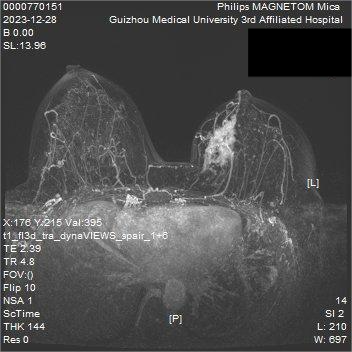

我院新引进的全球首款5G磁共振,配备专用乳腺线圈,具有无电离辐射、软组织分辨率高、特殊功能辅助成像等优点,是诊断乳腺疾病很好的影像检查手段。

乳腺肿块MRI图像具有多层面、多角度,分辨率高、图像清晰、血流分布情况一目了然等特点,能为乳腺疾病的精准诊断提供可靠保障。